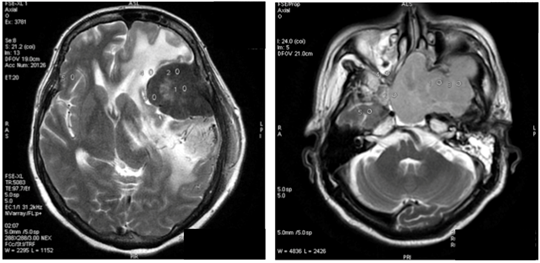

In our study showed that tumor volume as suggested by Hale et al. as the strongest predictor of atypical meningioma, didn’t always correlate with meningioma grade. In our samples there were 6 (37.5%) meningioma WHO grade I with tumor volume more than 50 cm3, with the biggest volume 252.4cm3 (Figure 1) and 1(33%) of atypical meningioma (WHO grade II) with tumor size 28.5 cm3. Hale also suggested that peritumoral edema as predictor of higher grade meningioma. In our study we found 1 case of anaplastic meningioma (WHO grade III) with mild edema and conversely, 44% of meningioma WHO grade I with severe edema (Figure 2). In that study also found that tumor along the falx and convexity were more often atypical than in skull base or posterior fossa. In this study, samples of meningioma WHO grade I mostly (37.5%) located in convexity, 25% in falx and in atypical meningioma WHO grade II turned out 67% located in skull base (Figure 3). That study also found that tumor necrosis was associated with an increased risk for atypical meningioma. In this study, we found 67% of atypical meningioma WHO grade II without tumor necrosis and 44% of typical meningioma WHO grade I with tumor necrosis (Figure 4). 1 case of anaplastic meningioma (WHO grade III) in our study had large tumor volume (>50 cm3), located in convexity and with tumor necrosis although there was one predictor that didn’t suit which in this case had mild peritumoral edema (Figure 5).

Figure 2 Female, 45 y.o with meningioma at right occipital convexity, tumor vol 26,2 cm3 surround with severe edema turned out as fibroblastic and microcystic type, WHO grade I.